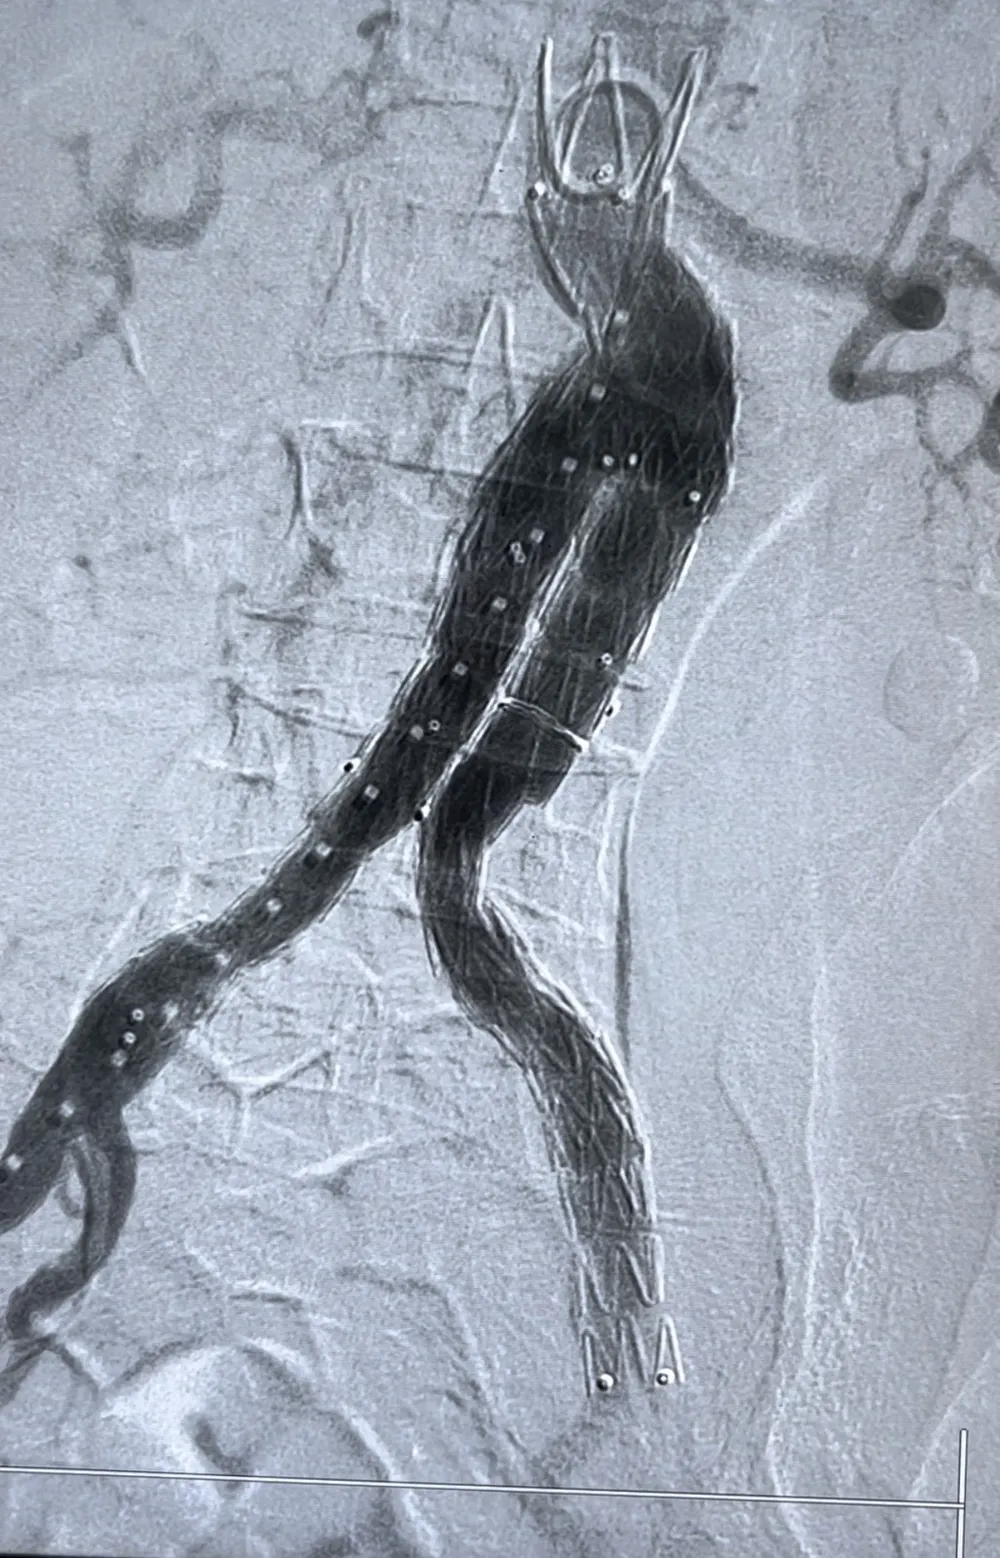

![]() |

Động mạch chủ của bệnh nhân sau khi can thiệp |

Các bác sĩ cấp cứu tim mạch can thiệp và hồi sức tim mạch của Bệnh viện Trung ương Huế đã phối hợp xử trí cấp cứu ổn định tình trạng huyết động. Ngay lập tức, tối cùng ngày, bệnh nhân được chuyển tới trung tâm can thiệp tim mạch để tiến hành can thiệp cấp cứu thành công đặt stentraft động mạch chủ bụng bít hoàn toàn túi phình lớn động mạch chủ bụng.